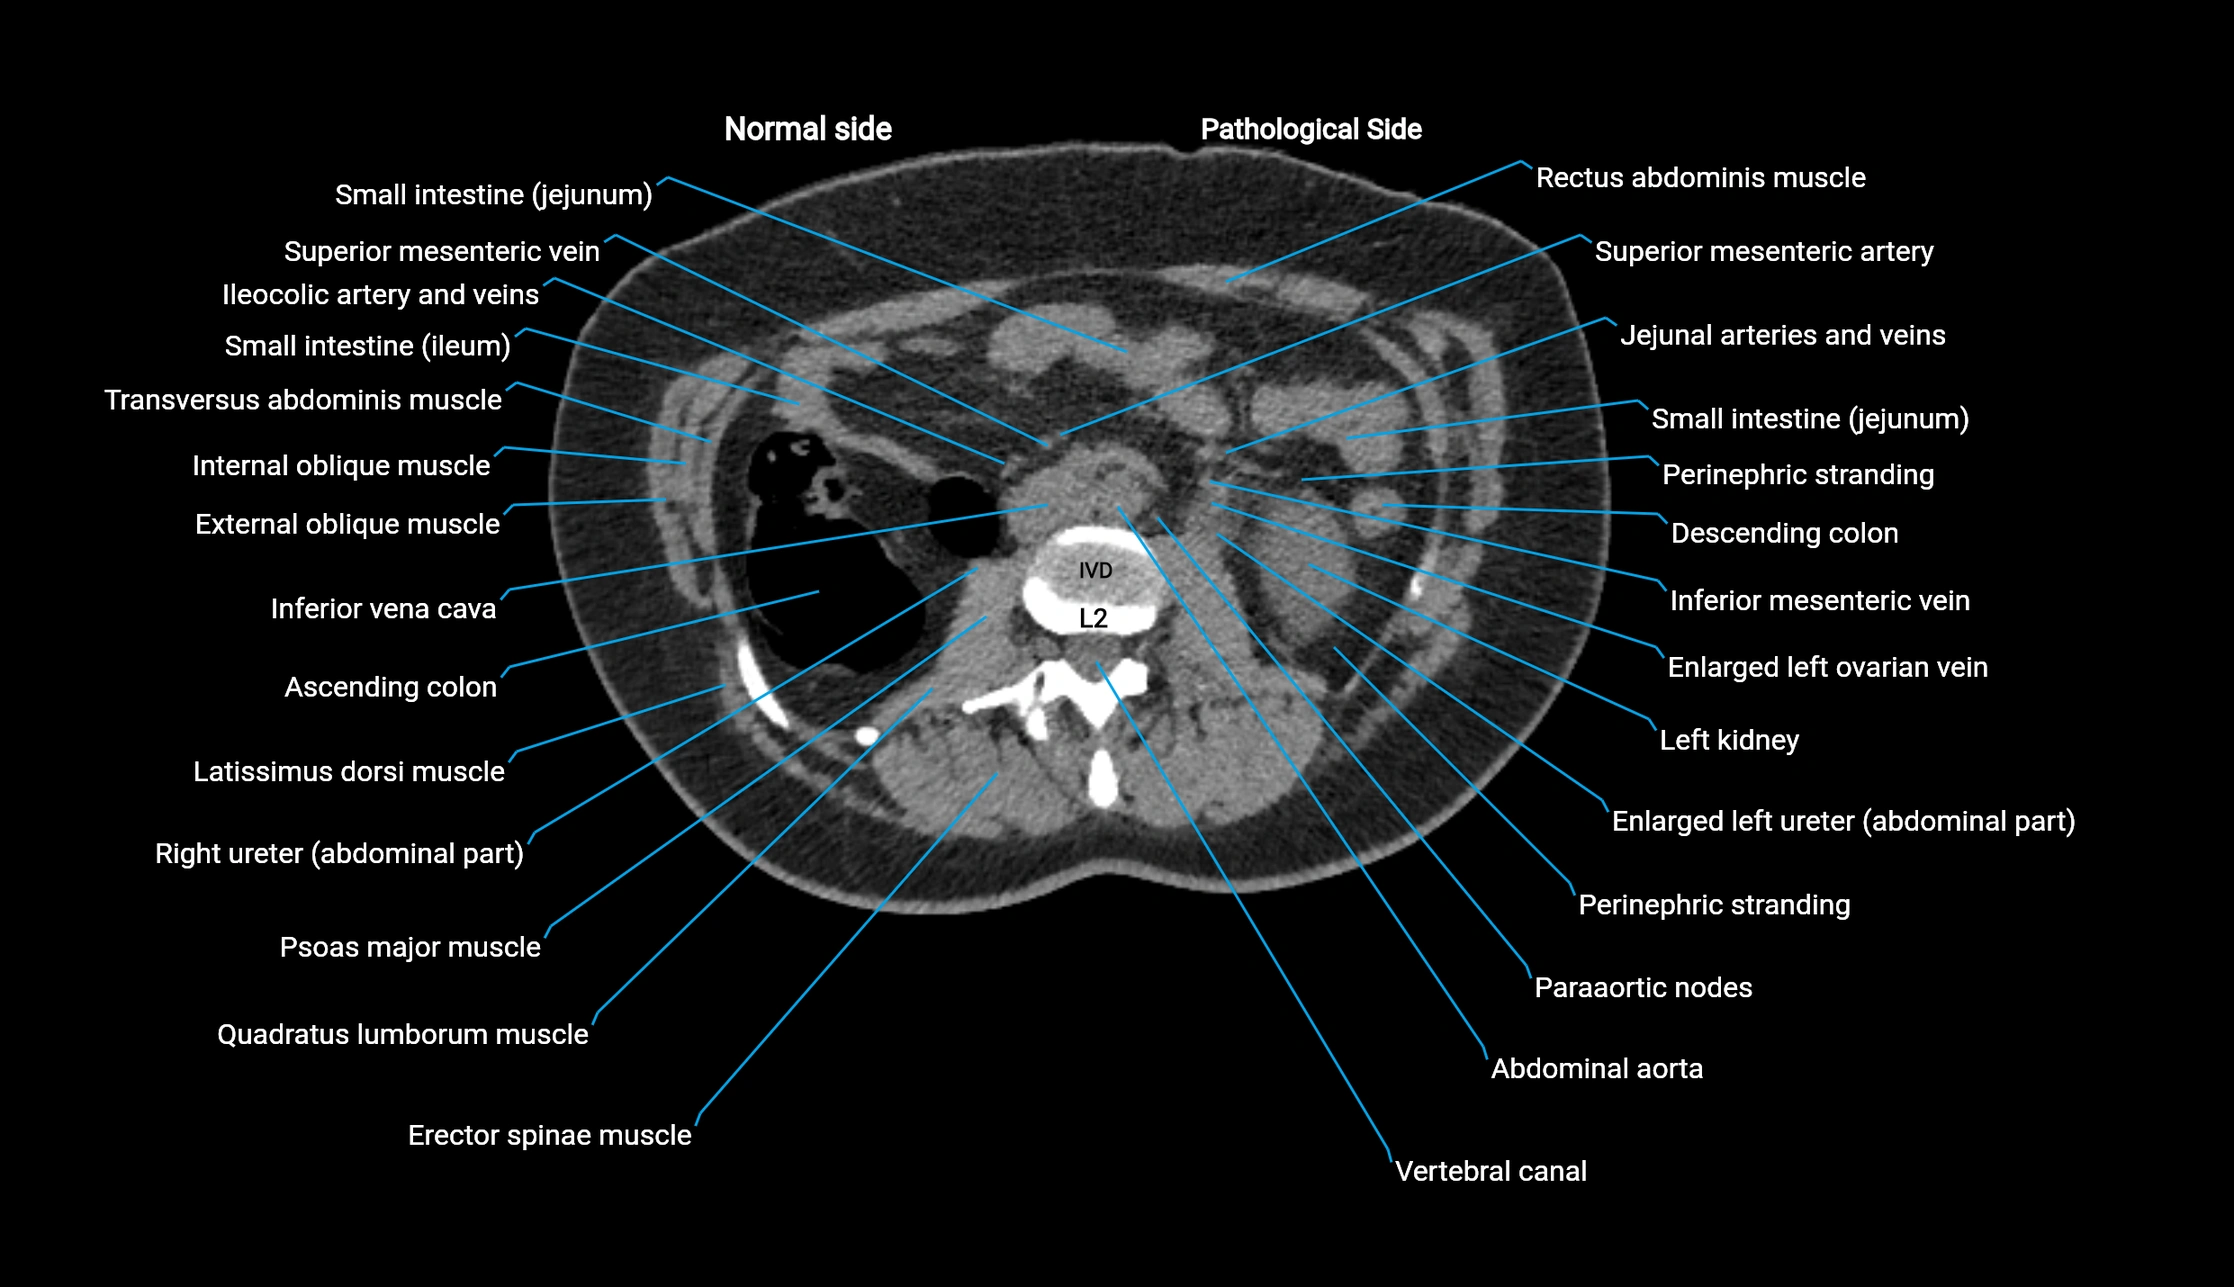

CT image

image